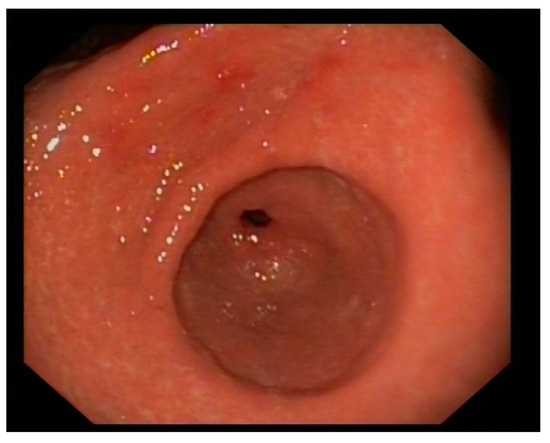

2. Case Description